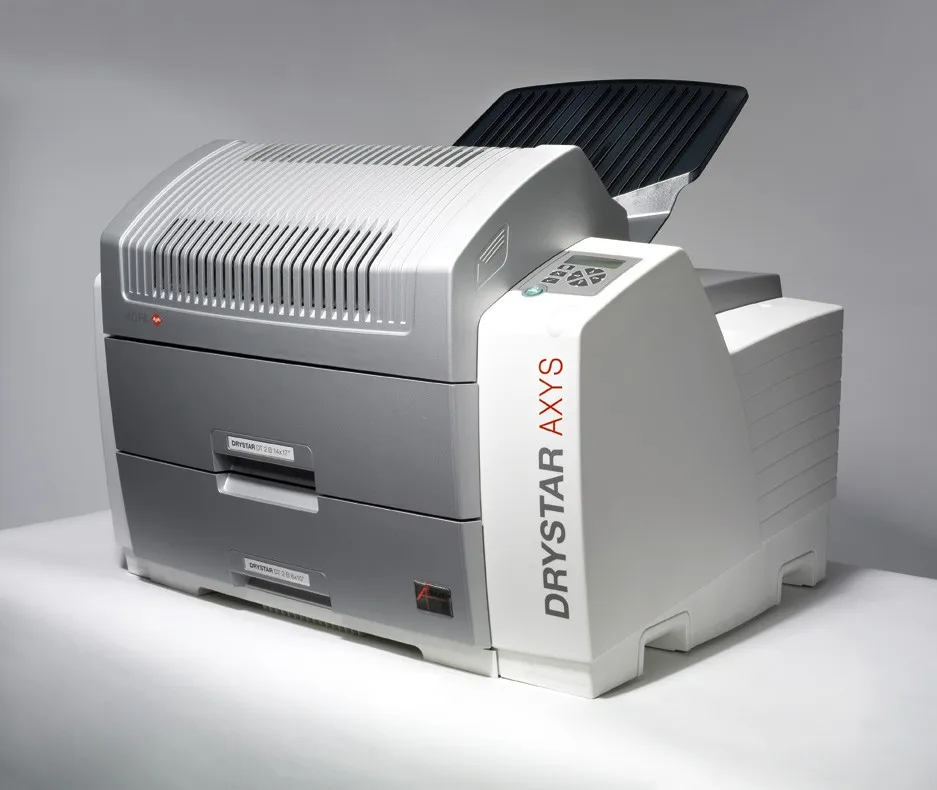

Лазерная камера для печати медицинских изображений на пленке стандарт dicom